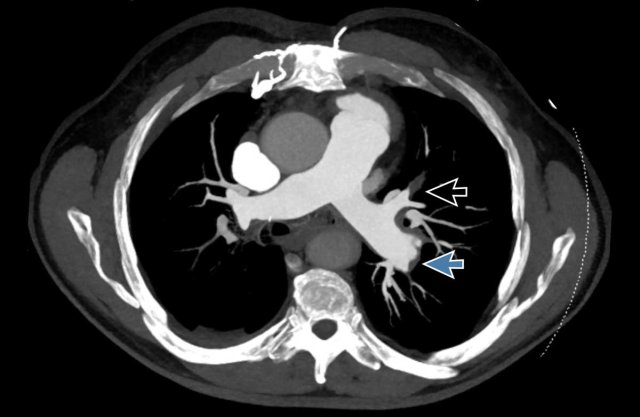

Images

These images are of a 59 y.o female at the emergency department,

nicely showing emboli at different levels.

Scroll through the images.

- Thrombus in the lobar artery to the right upper lobe.

- Thrombus in the orifice of the posterior basal segmental artery of the right lower lobe.

- Subsegmental thrombus in the anterior basal segment of the right lower lobe, a few divisions beyond the segmental artery.

- Thrombus at the segmental bifurcation of the left upper lobe.

- Thrombus continuing towards the periphery in the subsegmental artery.